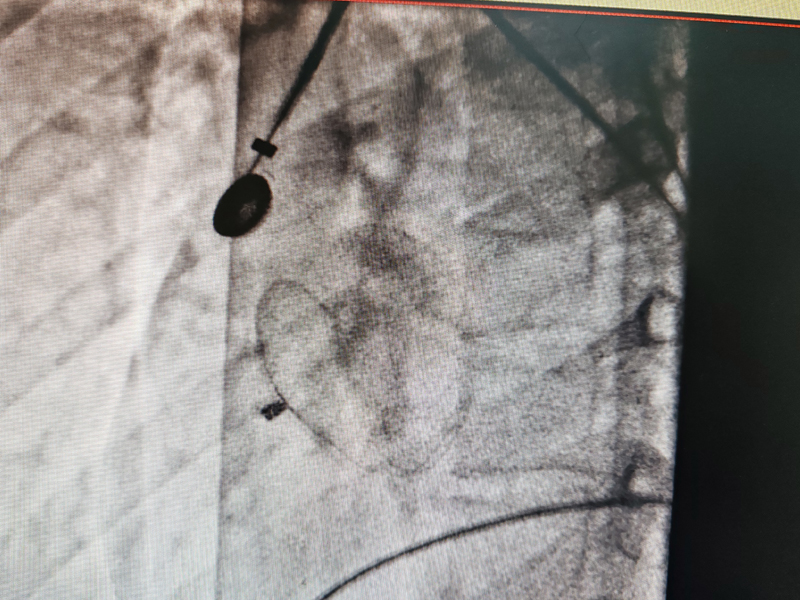

房缺介入封堵

心血管内科作为衡阳市医学会内科专业委员会主委单位及心血管内科专业委员会主委单位,2019年获批衡阳市心力衰竭防治重点实验室建设项目,2021年获批湖南省动脉硬化性疾病临床医学研究中心,2022年获批湖南省省级临床重点专科,目前结合心血管六大中心,四个病区,在IVUS引导下的冠脉精准个治疗、ECMO+IABP辅助循环支持下危重症患者的冠脉介入治疗、心脏瓣膜病TAVAR治疗、恶性心律失常的三维标测治疗、心血管疾病的危重症患者康复治疗等方面做到省内领先!